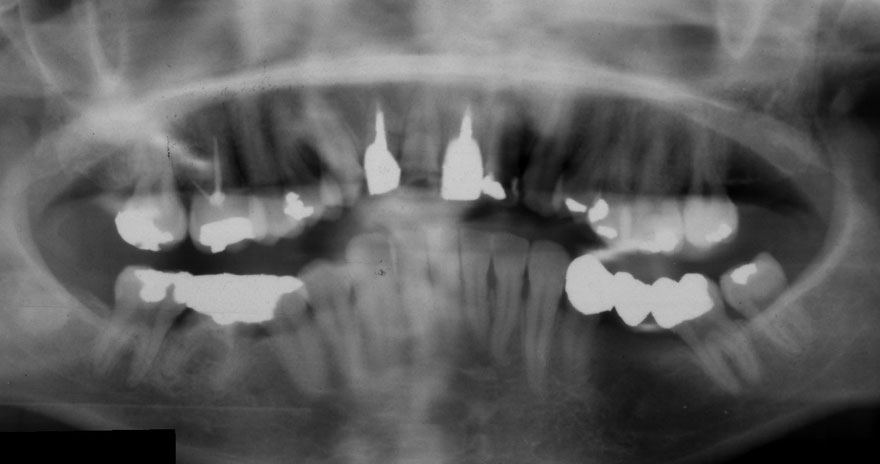

初診時 38歳 男性 平均歯槽骨喪失量:6.520mm

25年後 63歳

平均歯槽骨喪失量:8.57mm

25年間喪失量:-2.05mm

年間喪失速度:-0.08mm

(ケア頻度:1.38ヵ月ごと)